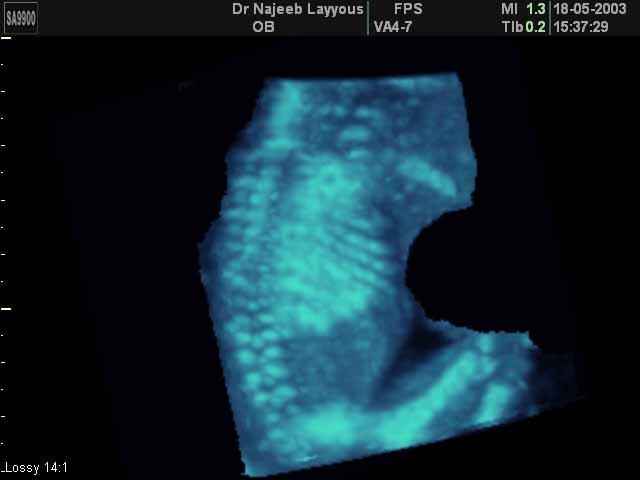

- Fetal Skeleton Ultrasound Photos